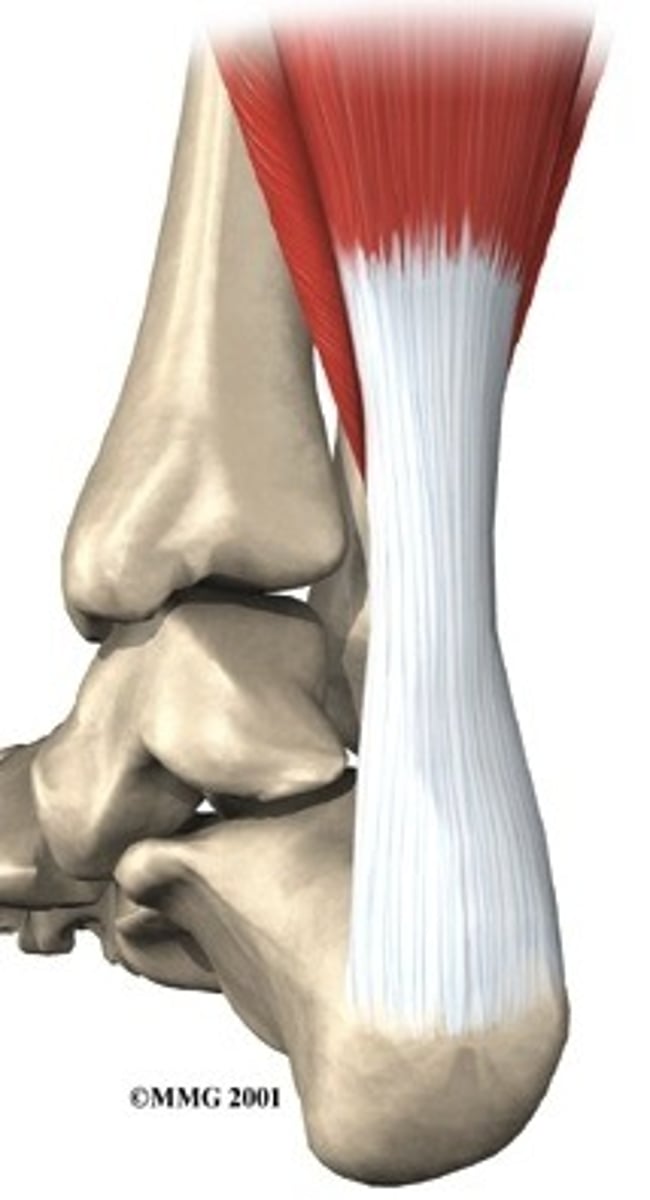

tendon

fibrous bands that connect bones to muscles

dorsiflexion

bending of the foot or the toes upward

plantarflexion

to point the toes down